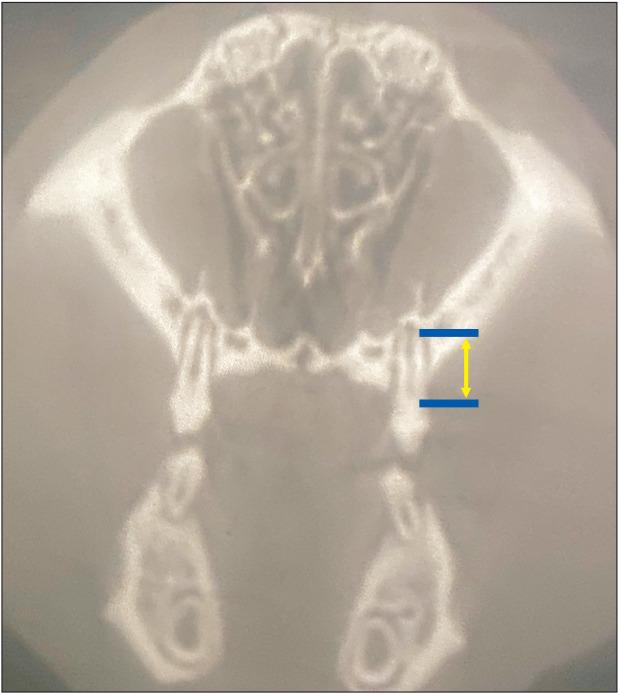

All maxillary molars on one side were moved against the combined incisors in 10 ten-week-old male Wistar rats. Under general anesthesia, a force of 25 cN was applied on either side using a Sentalloy closed coil spring. After placing the orthodontic appliance, vertical corticision was performed using a piezotome under local anesthesia, 2 mm mesial from the mesial root of the first molar on a randomly selected side; the other side served as the control. At the beginning of the treatment, and 2 and 4 weeks later, skull micro-computed tomography was performed. After image reconstruction, the distance between the mesial root of the first molar and the incisive canal, and the length of the mesial root of the first maxillary molar were measured. Moreover, the root resorption score was determined as described by Lu et al.

方法